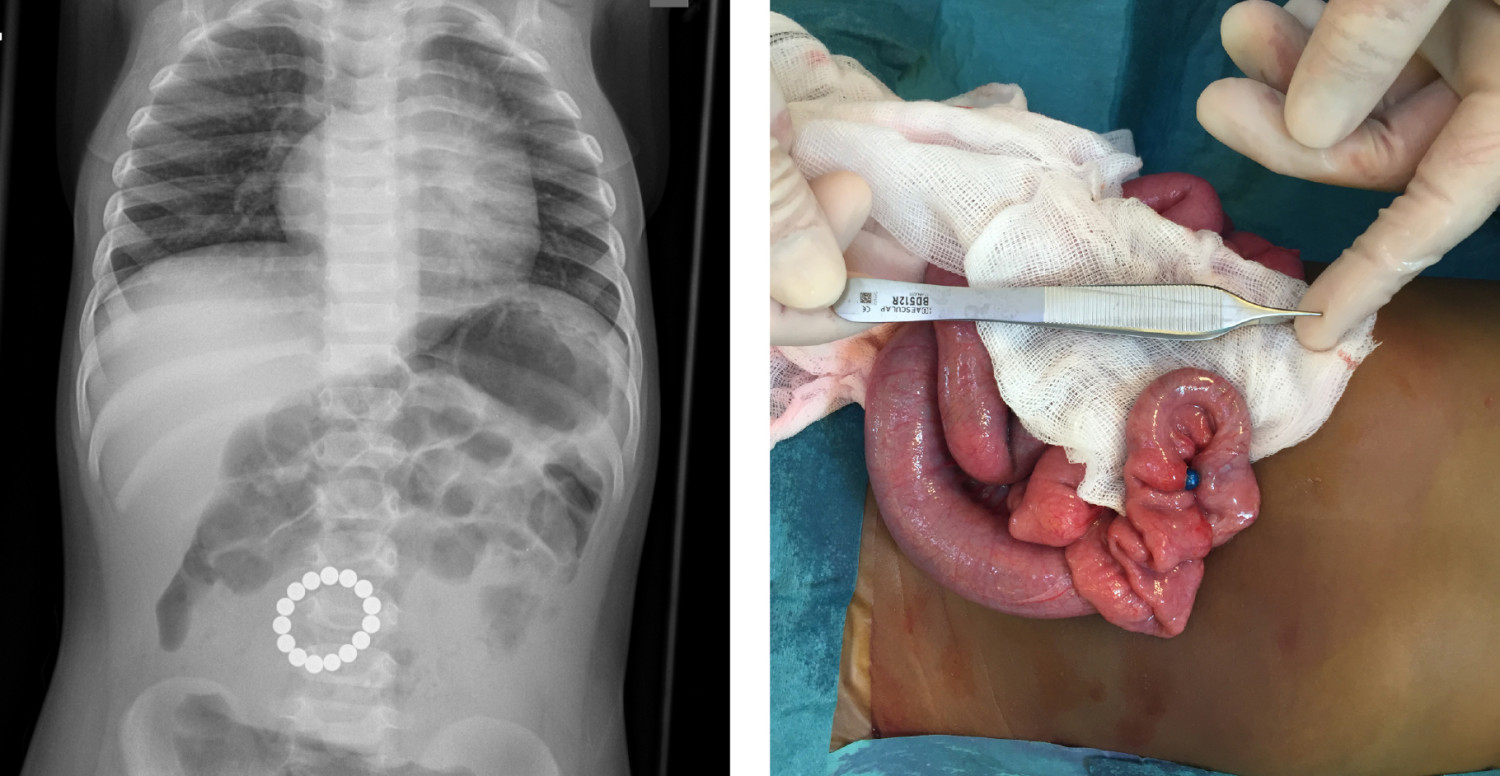

Røntgenbildet viser en krans av sirkulære fremmedlegemer intraabdominalt hos en ettåring. Pasienten ble innlagt med to dagers sykehistorie med oppkast.

Pasienten ble laparotomert. Man påviste en ring med magnetkuler i tynntarmen om lag 70 cm fra det treitzke ligament. En av kulene hadde erodert gjennom tarmveggen, som vist på bildet tatt peroperativt. Magnetkulene ble fjernet, og det var nødvendig med tarmreseksjon med primær anastomose. Pasienten ble utskrevet i god allmenntilstand femte postoperative dag, men ble innlagt på nytt to dager senere med sårruptur. Denne ble operativt korrigert, og barnet kunne utskrives tredje dag etter inngrepet.